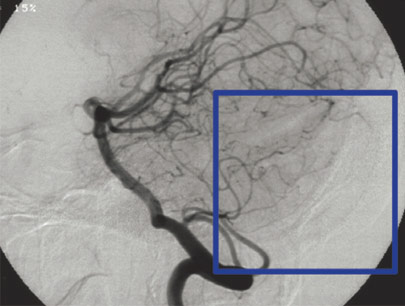

AVM (Arterivenous Malformation)

Kelainan pembuluh darah otak non-stroke

SEBELUM

SESUDAH

(Perempuan, 14 tahun)

Diagnosis: Malformasi Arteri-Vena Oksipital Kanan

Sebelum Gamma Knife

• Nyeri Kepala

3 bulan Setelah Gamma Knife

• Kebutaan menetap

• Penonjolan mata kiri berkurang

Diameter Nidus: 1.5 cm

Nidus tidak ada